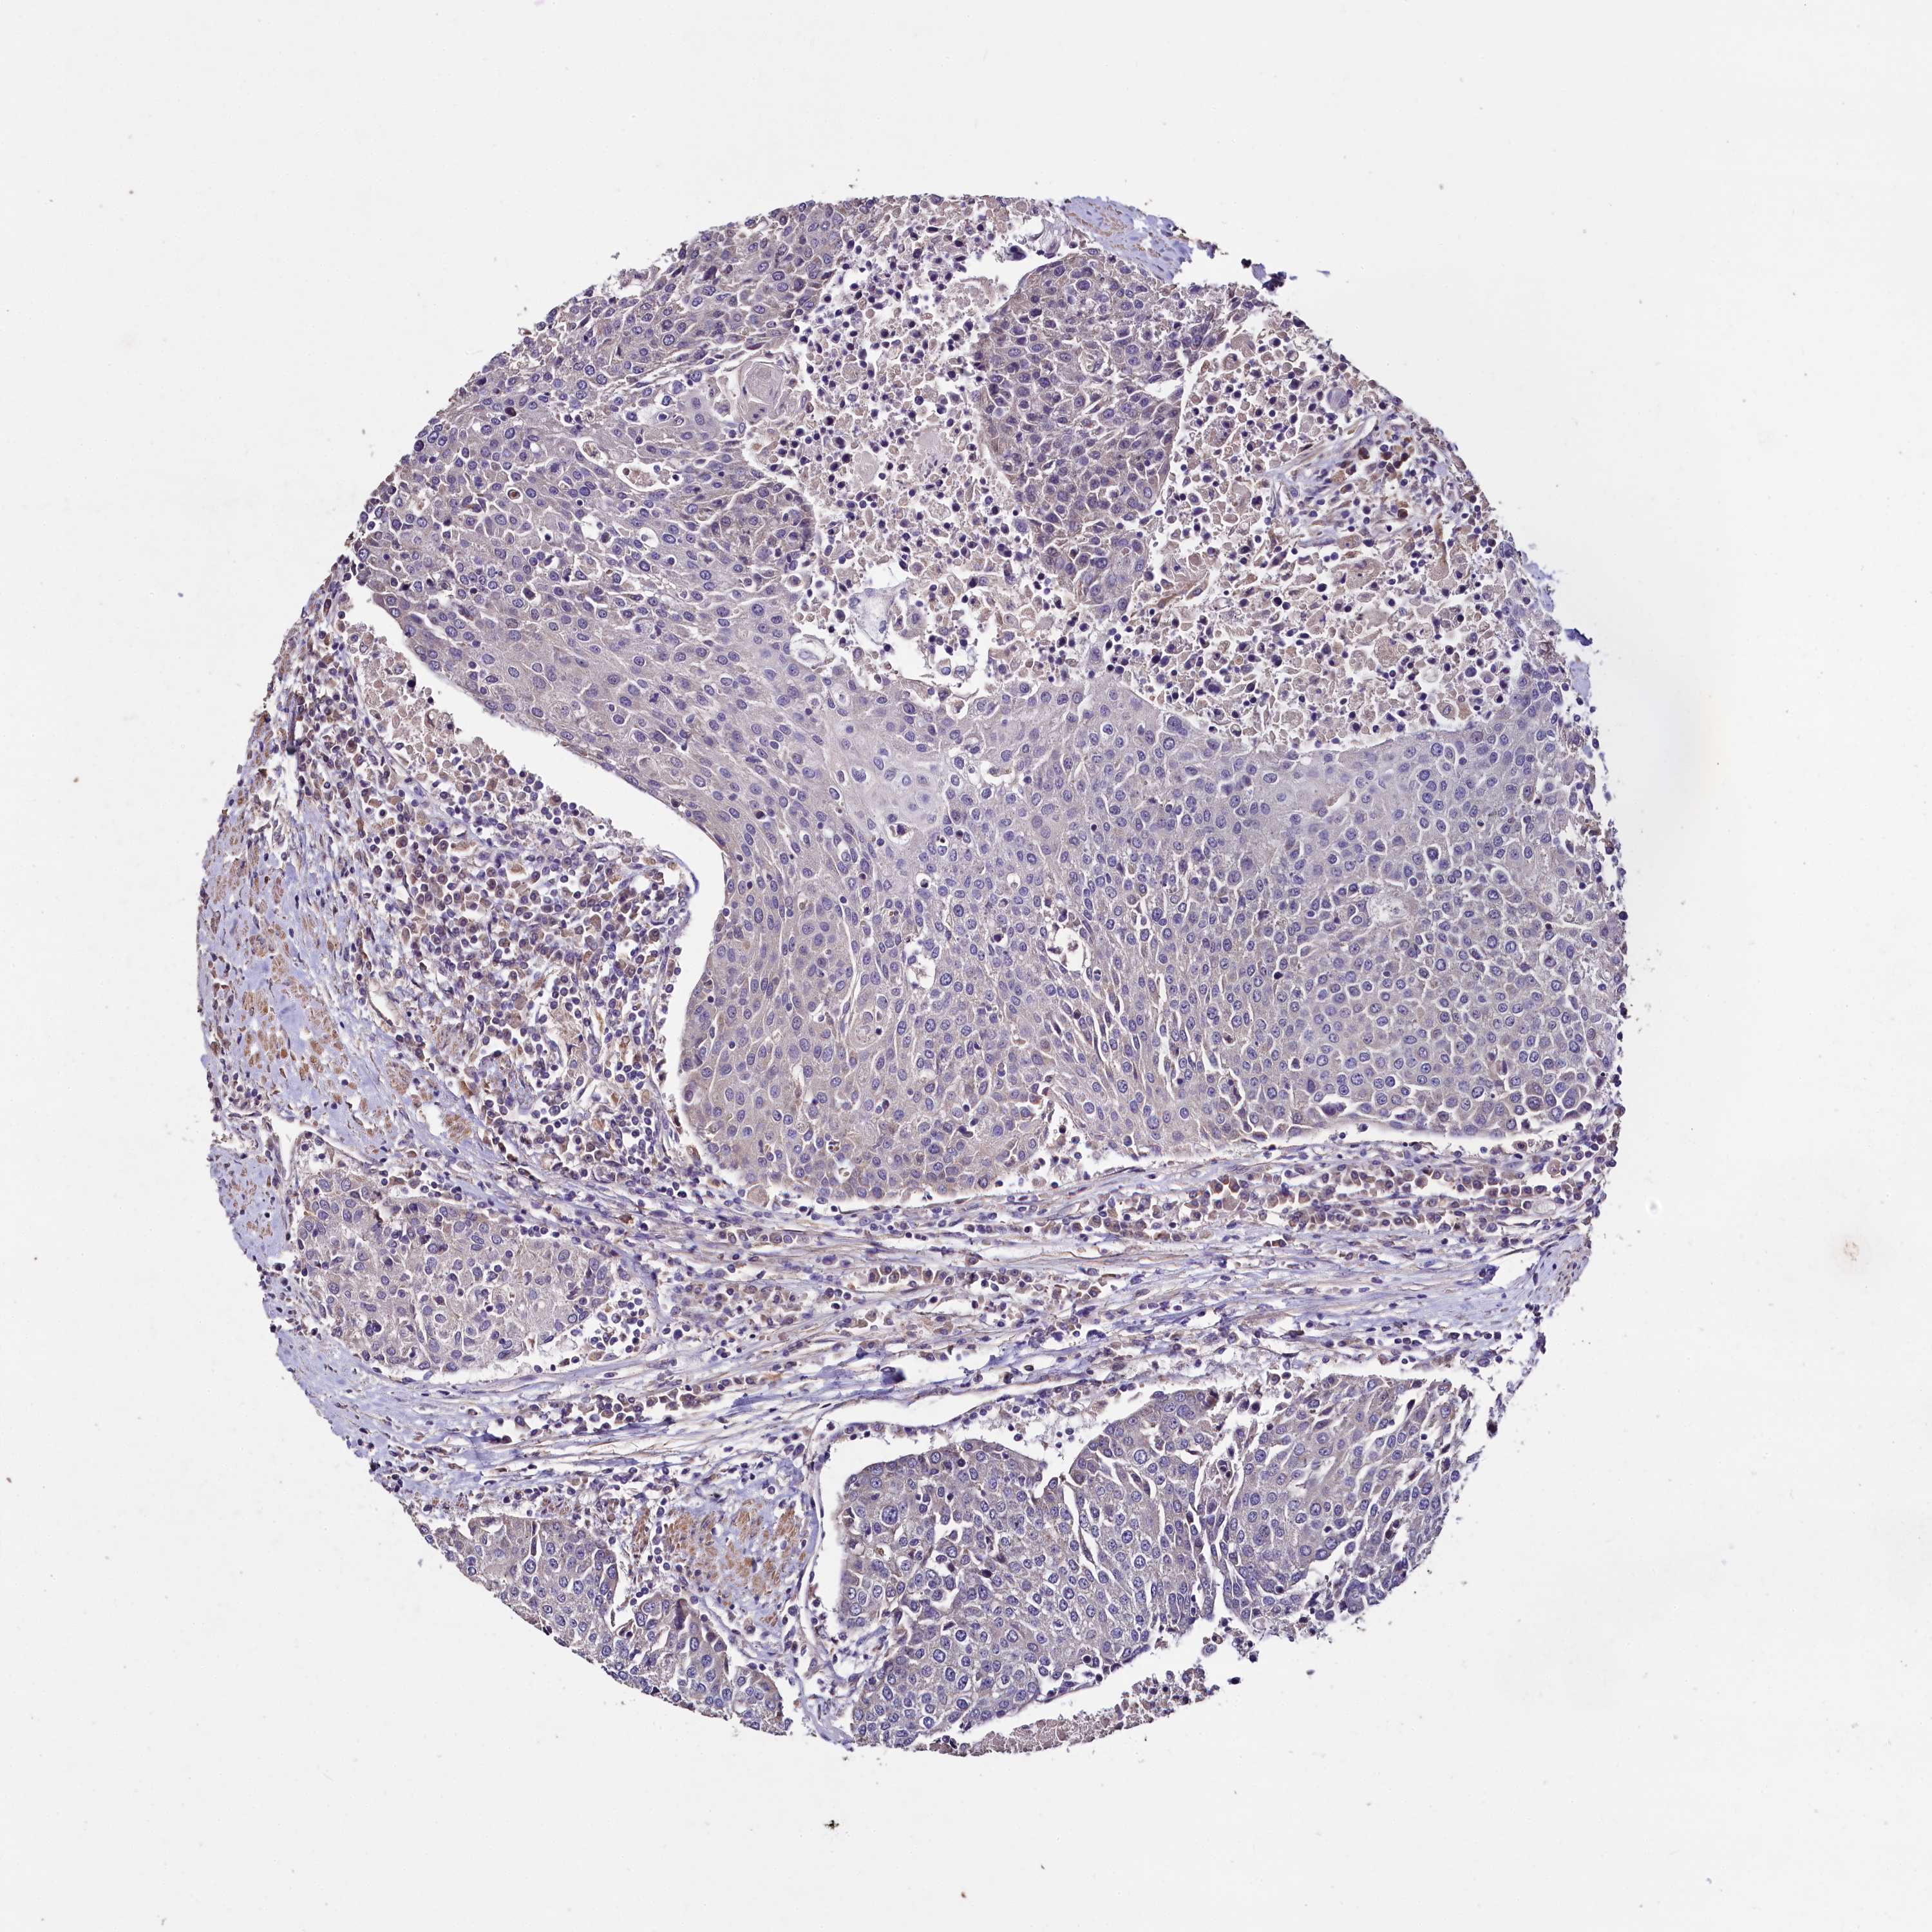

UROTHELIAL CANCER - Protein expressioni

A mouse-over function shows sample information and annotation data. Click on an image to view it in a full screen mode. Samples can be filtered based on level of antibody staining by selecting one or several of the following categories: high, medium, low and not detected. The assay and annotation is described here.

Note that samples used for immunohistochemistry by the Human Protein Atlas do not correspond to samples in the TCGA dataset.

Antibody stainingi

Antibody staining in the annotated cell types in the current human tissue is reported as not detected, low, medium, or high, based on conventional immunohistochemistry profiling in selected tissues. This score is based on the combination of the staining intensity and fraction of stained cells.

Each image is clickable and will lead to virtual microscopy that enables deeper exploration of all samples and also displays staining intensity scores, fraction scores and subcellular localization as well as patient and tissue information for each sample.

Antibody HPA040918

Staining

High

Medium

Low

Not detected

Intensity

Strong

Moderate

Weak

Negative

Quantity

>75%

75%-25%

<25%

None

Location

Nuclear

Cytoplasmic/membranous

Cytoplasmic/membranous,nuclear

Urothelial carcinoma, Low grade

Urothelial carcinoma, High grade